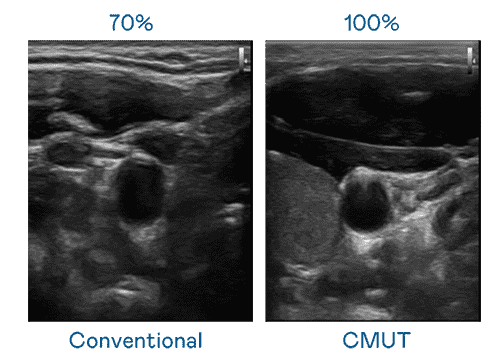

CMUT 技术是一种用电容式微机电元件来产生超音波讯号的技术。。。。与传统 PZT 压电式技术相比,,,CMUT 频宽增加 30%,,,,更宽频的超音波讯号让影像解析度大幅提升,,,是实现高影像品质医疗超音波扫描、、、促进精准医疗发展的关键技术。。

大频宽带来超清晰影像

超音波影像的解析度高低,,首先取决于探头能发出的讯号频宽。。。赏金国际 CMUT 可提供高清晰的超音波讯号,,,提供高频宽、、高灵敏度、、、、影像纹理细节更高的超音波影像,,,,协助医护人员缩短影像判读时间及利用精准的医疗影像进行诊断。。